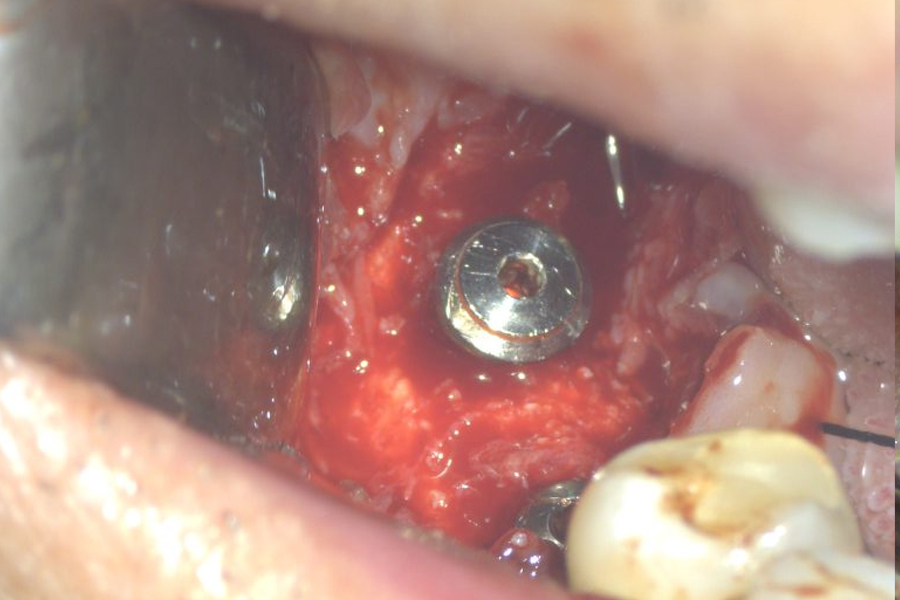

こちらの患者様は2002/02/21、16年前に当医院で私がインプラント手術致しました。

16年後の定期健診でインプラント周囲炎を起こしていることを発見致しました。

レントゲン上で左のインプラント周囲の骨が吸収しているのが観察されます。(2018年2月撮影)

インプラントは骨と結合(oseoinyerration)しやすいように表面の構造が塑像になっていてそのことが一旦、プラークで汚染されるとインプラント体を清掃して無菌的にしてインプラント周囲炎を治癒させる方法がありませんでした。

Er:Yagレーザーによりこの塑像な構造を洗浄して歯石・細菌性プラークを綺麗に除去することが出来るようになりました。

手術時と術後4ヶ月の写真です。

4ヶ月前のオペ時のビデオです。